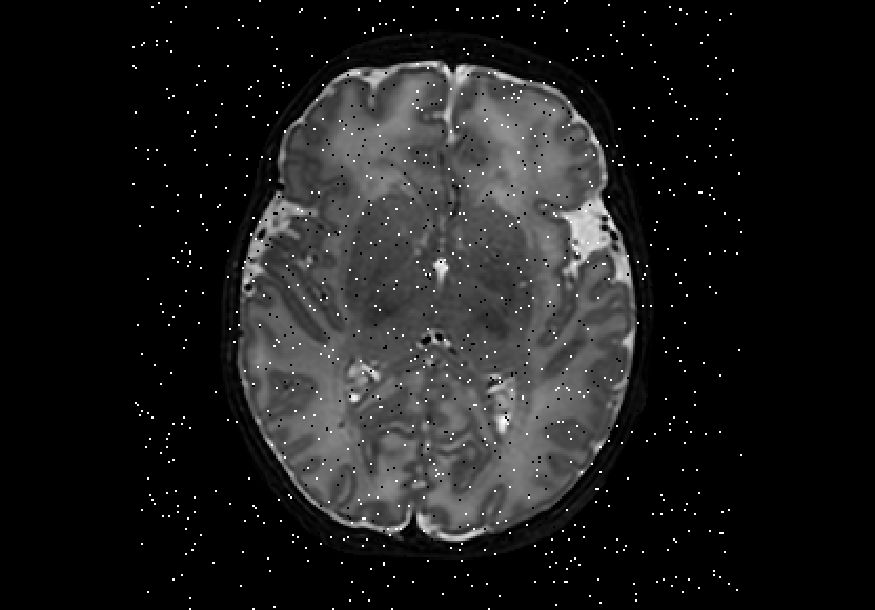

We also explored impulse noise corruptions, such as those introduced by noisy communications channels, faulty memory locations, or damage in channel decoders [6]. The impulse noise generating filter we used in this study is based on the salt-and-pepper (SNP) technique, which randomly generates black and white pixels on the image of interest. The function we used takes into account a parameter called prob, where 0 prob 0.5. A random number is generated for each pixel; if it is less than prob then the function paints the pixel with black, if it is greater than 1-prob then it paints the pixel with white, otherwise the pixel is left unchanged. In other words, the higher the value of prob, the noisier the output can become. We used different values for prob, in particular prob ={0.01, 0.03, 0.05, 0.07, 0.10, 0.15, 0.20}, to create seven different noisy datasets named snp_prob. Examples of axial slices are shown in Figure 4.